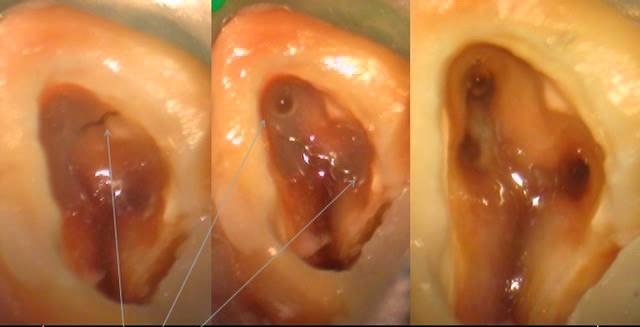

• получение четкого объемного изображения исследуемой полости;

• возможность установить точное расположение каналов;

Лечение зубов под микроскопом позволяет провести грамотную диагностику. Использование оптики дает возможность сократить количество рентгеновских исследований. При осмотре под микроскопом врач имеет возможность различать ткани по цвету, структуре и степени прозрачности. Получение объемного изображения позволяет точно установить, на какой глубине находится исследуемый объект.